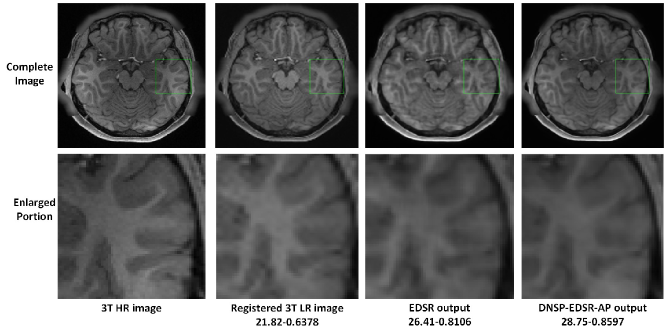

Figure 12: Comparisons of top 4 methods for an image in ADNI dataset for scale factor of 2. A small portion of the images (marked by green box) in the first row is zoomed in and shown in second row. The numerical figures constitute the respective PSNR-SSIM values.

Refer to caption

Quantitative results are reported in Table IV. As can be observed, DNSP-EDSR-AP achieves superior performance over the state of the art EDSR network. Figures 19 and 20 show visual comparisons for example images from both the datasets. It can be observed that the DNSP-EDSR-AP enhanced image is closer to ground truth image compared to EDSR.

Figure 20: Comparisons of EDSR and DNSP-EDSR-AP on 3T3T-T1 dataset [48]. The numerical assessment is shown as PSNR-SSIM. The DNSP-EDSR generates the best results both numerically and visually compared to EDSR for 3T3T-T1 dataset.